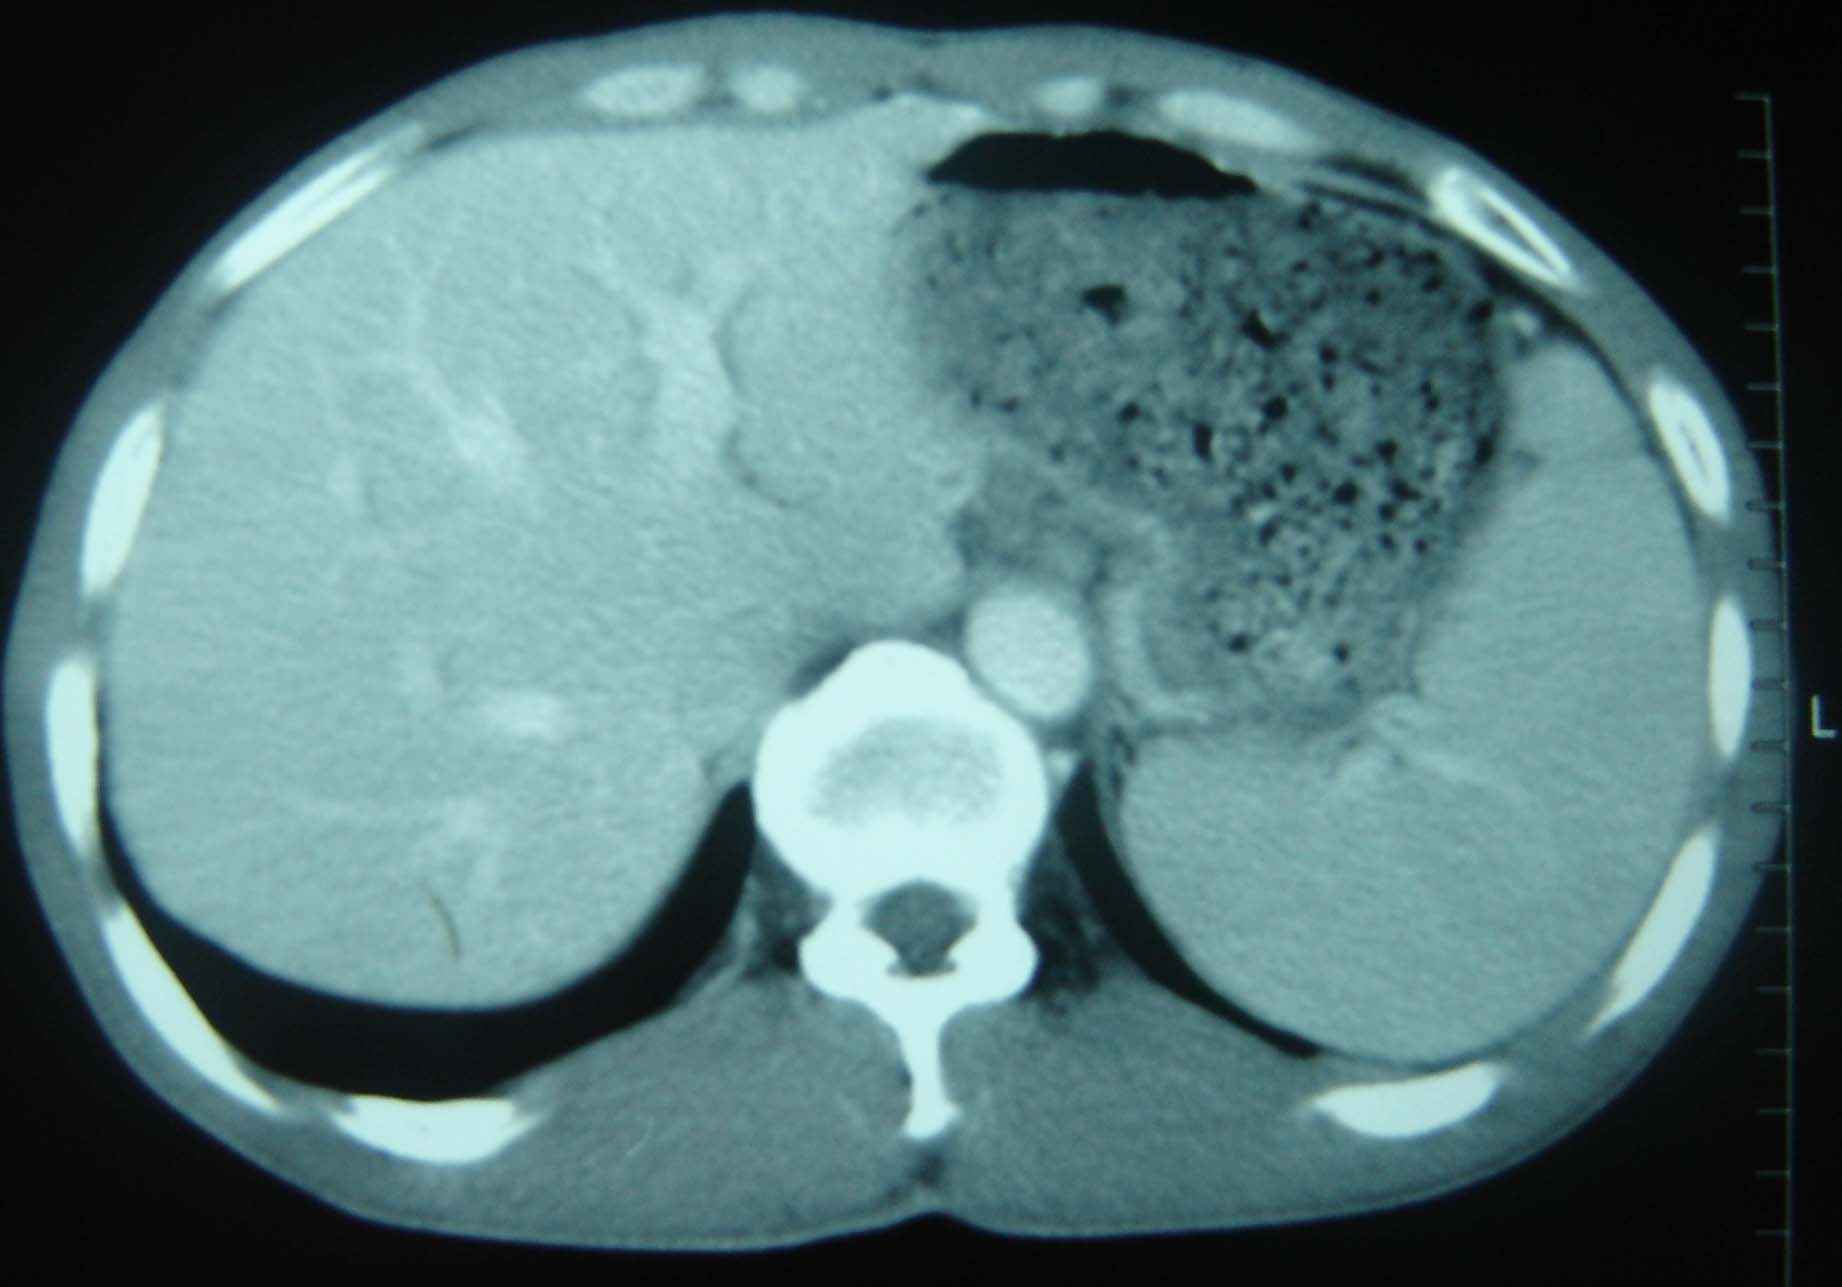

标题: CT25321:两肺多发结节 请会诊 [打印本页]

标题: CT25321:两肺多发结节 请会诊

男 、43岁,咳嗽胸痛,装修工,平时接触粉尘较多,有吸烟史10多年,纤维支气管镜检查未发现异常,胃镜、腹部b超检查亦未发现异常,颈部淋巴结活检未发现肿瘤细胞。

不能排除转移,如果不能找到原发灶,只有短期随访。

结节病?转移瘤?

1)考虑双肺及胸膜多发性转移瘤。2)肺气肿。